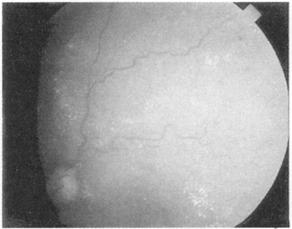

在熟悉之前你需要看一些视网膜图,花时间去注意黄斑,为一淡红色斑点。按顺序描述你的所见为佳,寻找背景,不是乳头或黄斑,而是出血和渗出,检查视网膜血管,注意粗细和规则——小动脉的直径是静脉的2/3,分布规则。正常的视乳头和糖尿病、高血压、乳头水肿和视神经萎缩见图(图151~155)。

图151 正常的视神经盘和视网膜

图152 糖尿病眼底的改变,可见斑点状出血和渗出

图153 高血压病眼底改变,可见血管屈曲

图154 视神乳头水肿,可见神经盘处模糊

图155 视乳头肥大,可见神经盘变清晰、苍白